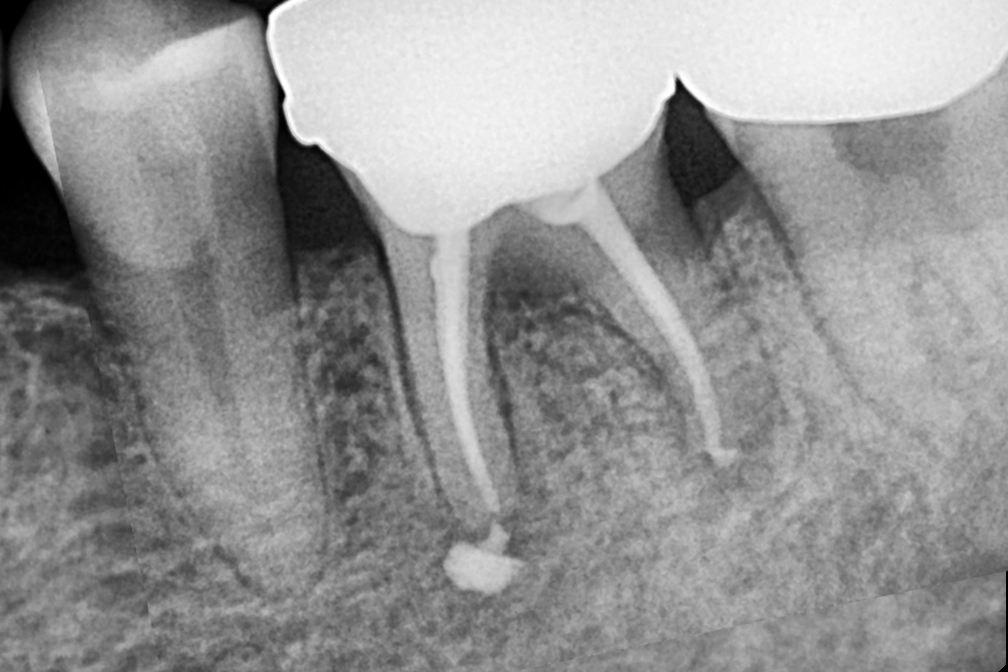

신경치료

After 2026년 4월 11일-

위 전후사진은 이미지사진으로 실제 눈으로 보는 것과는 다를 수 있으며, 환자의 치아상태과 방법에 따라 치료결과가 다를수 있습니다.

사진의 날짜는 촬영날짜이며 치료의 기간이 아님을 알려드립니다.

치료 후 치아표면의 탈회 , 충치, 치근흡수 등의 부작용이 있을 수 있습니다.